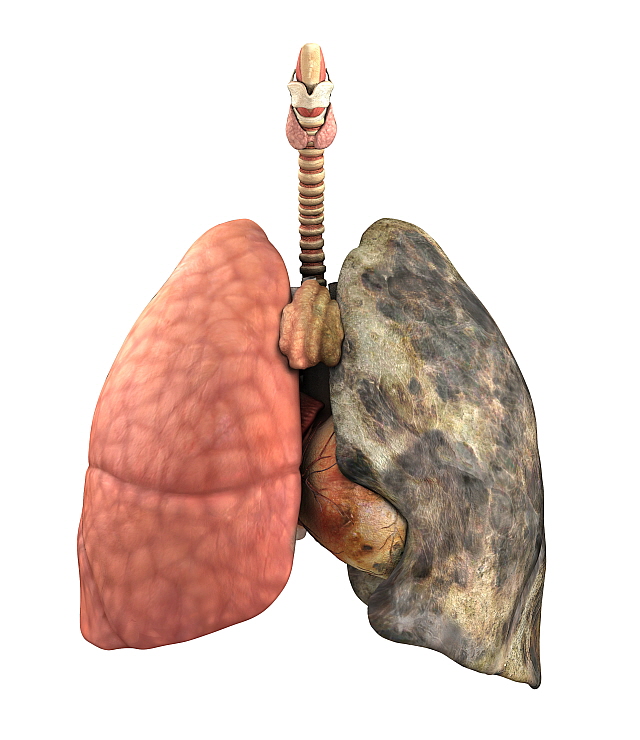

안녕하세요! 오늘은 ‘폐렴’의 증상에 대해 자세히 알려드릴게요

요즘처럼 일교차가 크고 면역력이 떨어지기 쉬운 계절에는

감기나 독감 뒤에 폐렴으로 악화되는 경우도 많습니다.

특히 노약자, 만성질환자, 어린아이에게는 치명적일 수 있죠.오늘은 초기에 알아두면 생명을 지킬 수도 있는

폐렴의 주요 증상 10가지를 아주 상세히 알려드릴게요.

폐렴 증상 폐렴 증상